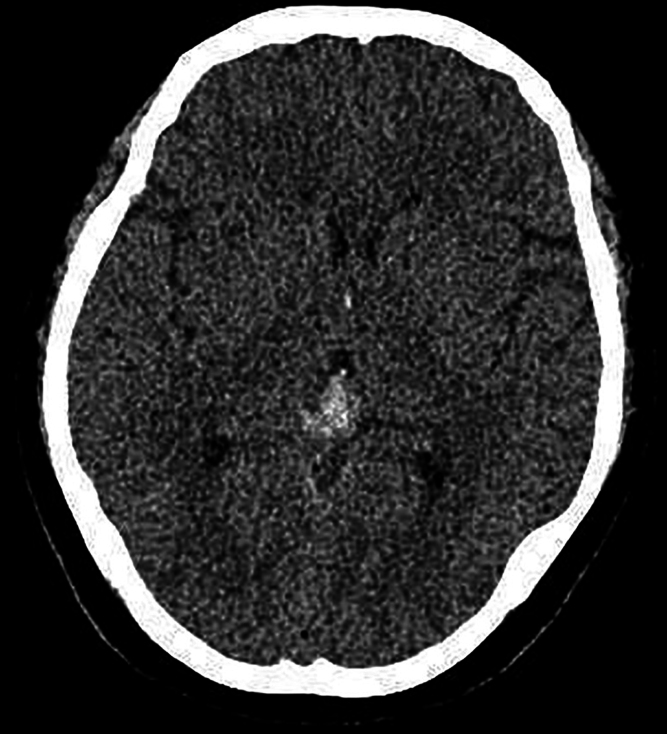

Background: Primary pineal melanoma is a rare tumor characterized by a high propensity for progression and recurrence. The imaging complexity of the melanoma will pose significant challenges for preoperative diagnosis. Definitive diagnosis necessitates histopathological examination.

Observations: The authors present the case of a 49-year-old woman presenting with headache accompanied by nausea and vomiting. Imaging revealed a pineal tumor with subarachnoid hemorrhage. She underwent her first craniotomy at another hospital. Four months after surgery, she was sent to the authors' hospital for a second craniotomy due to recurrent cerebral hemorrhage. The postoperative pathological diagnosis was malignant melanoma in the pineal region.